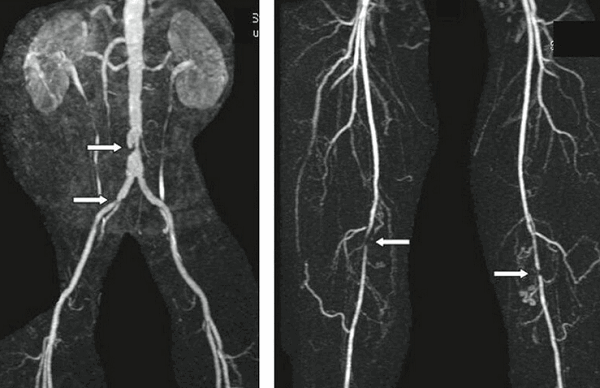

Атеросклероз сосудов нижних конечностей может проявляться синдромами перемежающейся хромоты, когда у человека появляются боли в икроножных мышцах при ходьбе, но она исчезает в состоянии покоя. При дальнейшем развитии заболевания болевой синдром сохраняется и в покое, а в более тяжелых и запущенных случаях развивается трофическая язва и гангрена конечностей.

Для выявления атеросклероза сосудов сердца, шеи и конечностей в медицинских центрах СПб активно применяется доплеровское УЗИ (допплерография). Это быстрый, безопасный и по сравнению с МРТ и КТ более дешевый способ сосудистой диагностики. С его помощью врач оценивает кровоток, а в месте его нарушения ищет признаки бляшек.

В визуализации атеросклероза нижних конечностей УЗИ признается основным скрининговым методом, поскольку диагностическая ценность МРТ, КТ И УЗИ в этом случае сопоставима, а вот стоимость томографии существенно выше. Однако, основная проблема с ультразвуковым исследование заключается в его диагностической субъективности, так как его результаты полностью зависят от опыта и движения рук специалиста, выполняющего данное исследование.

Холестериновые отложения в коронарных сосудах лучше всего искать с помощью КТ сосудов сердца. Информативность ультразвука здесь снижается из-за костей ребер. Также у УЗИ есть ряд ограничений при обследовании тучных пациентов и больных после операции брюшной полости. МР-коронарография тоже весьма информативна в визуализации атеросклеротических изменений коронарных артерий, но на данный момент ее можно качественно проводить на супермощных томографах 3 Тесла, обследование на которых в 2 раза дороже КТ-коронарографии. Методика МР-томографического контрастированного исследования атеросклеротических поражений крупных сосудов может быть использована как дополнительная независимая техника исследования атеросклероза. Она позволяет улучшить диагностику риска расслаивания, разрыва аневризматических атеросклеротических поражений и выработать дополнительные критерии к их опережающему хирургическому ведению.

Признаки атеросклероза (пораженные участки указаны стрелками) на МРТ